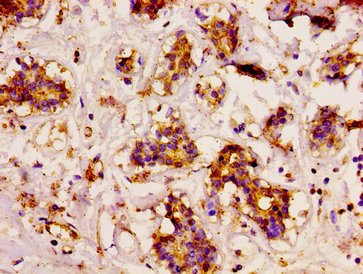

IHC image of CSB-PA004932LA01HU diluted at 1:200 and staining in paraffin-embedded human breast cancer performed on a Leica BondTM system. After dewaxing and hydration, antigen retrieval was mediated by high pressure in a citrate buffer (pH 6.0). Section was blocked with 10% normal goat serum 30min at RT. Then primary antibody (1% BSA) was incubated at 4°C overnight. The primary is detected by a biotinylated secondary antibody and visualized using an HRP conjugated SP system.